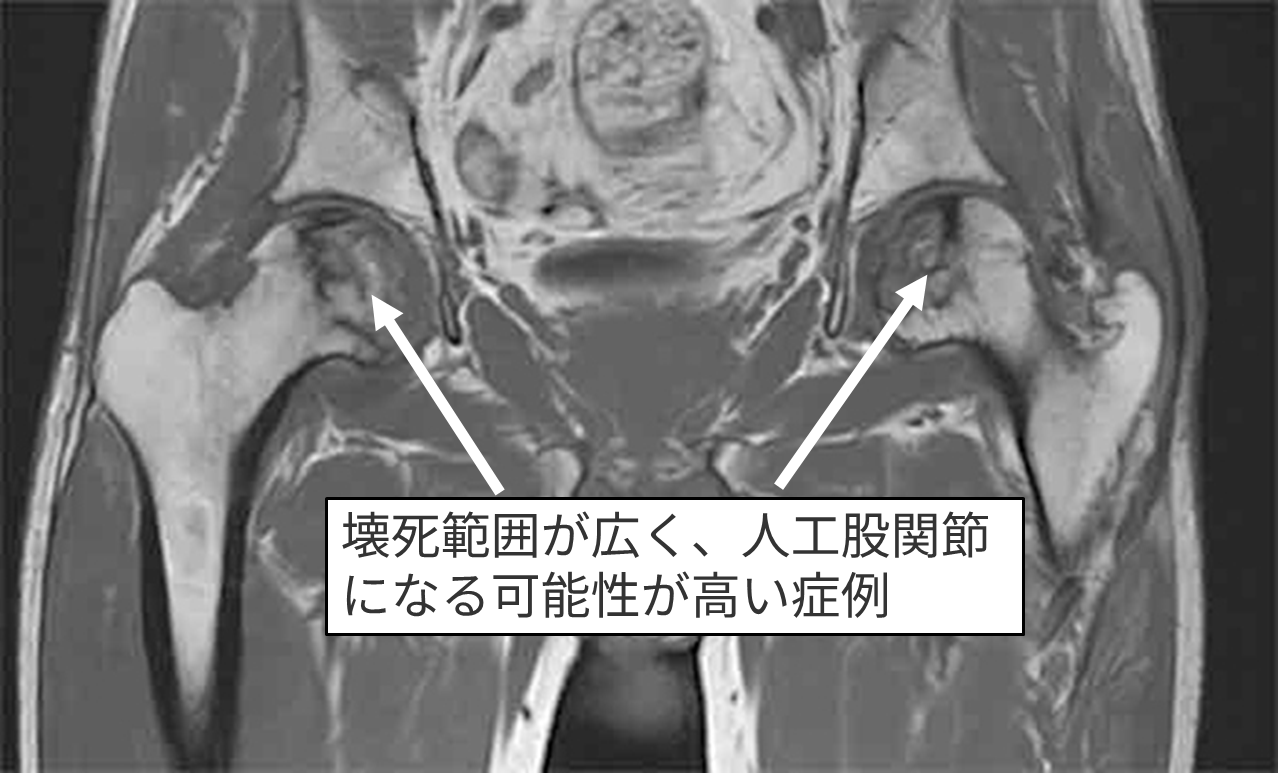

MRI検査

右Type C1 左Type C1

右Stage 2 左Stage 3A

壊死範囲が広いタイプでかかりつけ医から「いずれ人工股関節になる可能性が高い」と言われた

再生医療希望で受診両側の再生医療手術を施行